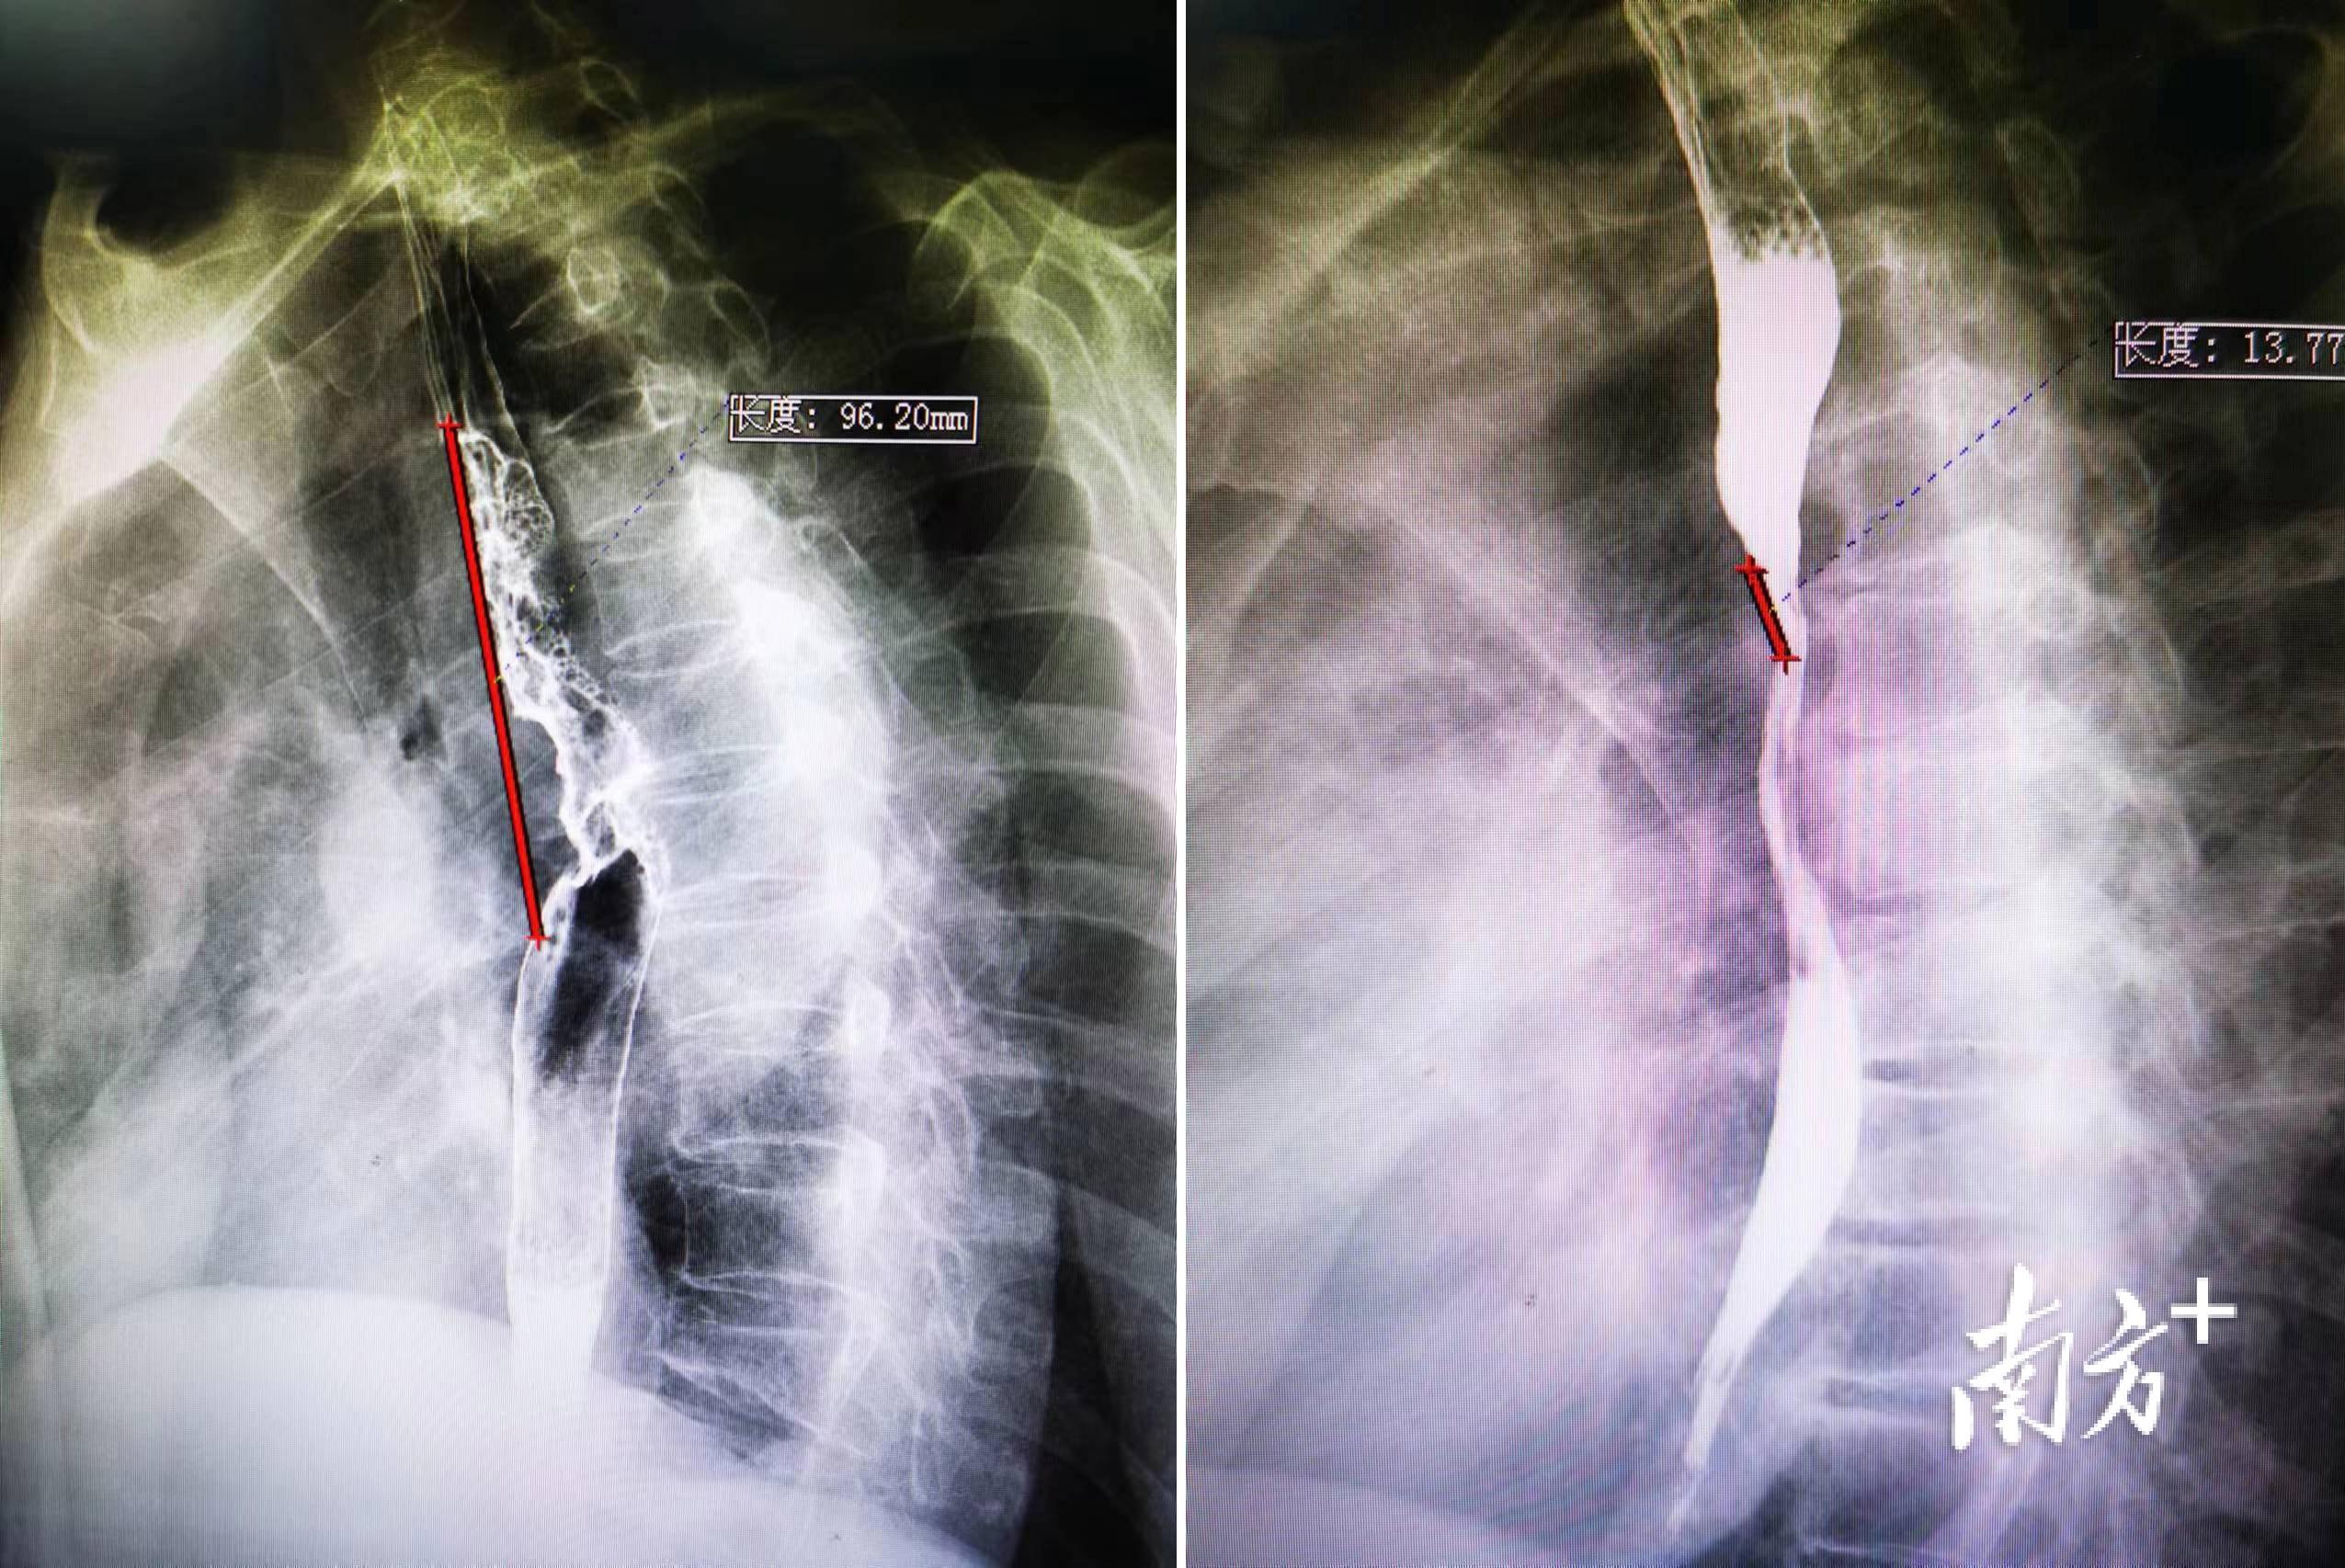

新辅助治疗前后病变对比。 受访者供图

据介绍,在3月25日举办的食管癌手术培训班上进行演示的正是一位此前已进行新辅助免疫治疗的患者。这名患者在今年1月30日开始用药进行新辅助免疫治疗,经过两个疗程的治疗后,彼时已将近9厘米的肿瘤在手术前缩小为1.8厘米,有利于医生在手术时进行更彻底的切除。